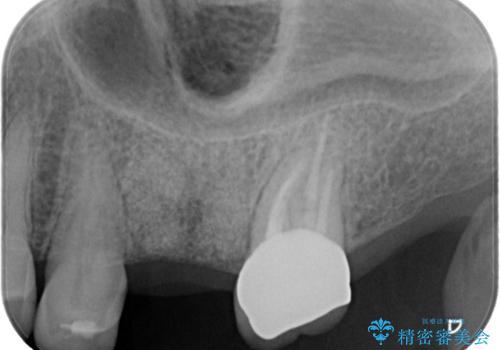

- 痛みを主訴に来院されました。

歯牙の破折を認めたため抜歯をし、インプラントにて咬合回復をしました。